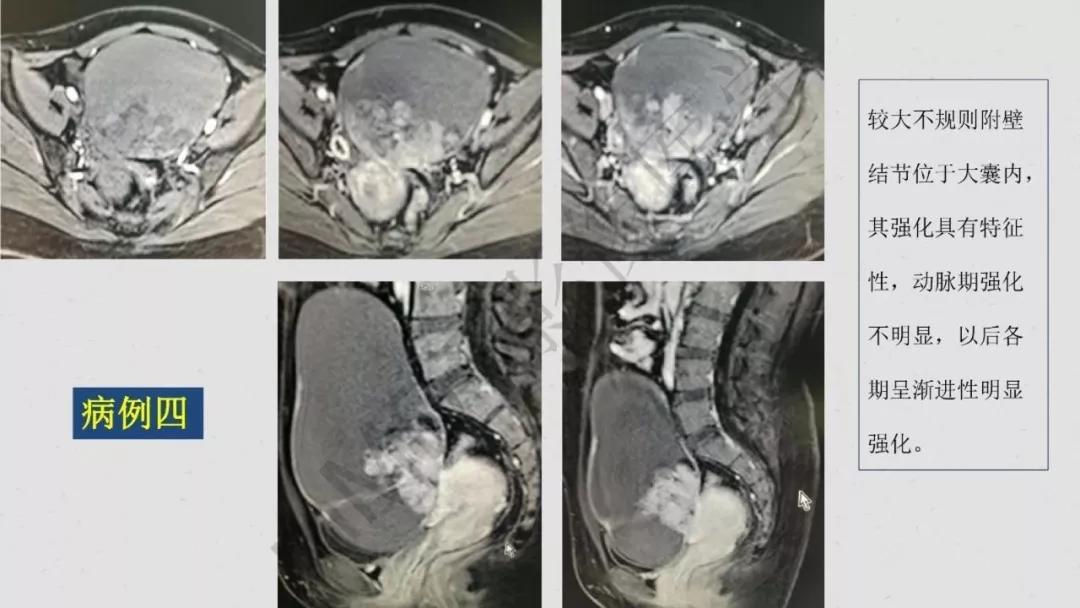

性索间质性肿瘤:较少见,良性多,多数肿瘤具有内分泌功能,可伴有内分泌症状及子宫内膜增生,内膜癌,乳腺疾病。多呈囊实性及实性肿块,界清,形态规则或欠规则,少有壁结节,多数呈实性伴有大片变性低密度改变,轻中度强化。